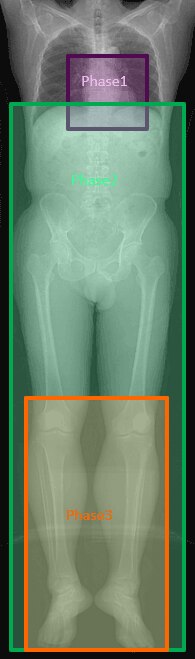

Phase1. 上行大動脈にROIを配置しスマートプレップ法にて心臓を撮影

Phase2. 13秒後に下肢動脈を約30~40秒かけてゆっくり撮影(大動脈を含む場合は胸部から)

Phase3. 膝窩動脈以下3分枝をもう一度撮影(血流速度が極端に遅い症例の備えとして)

※ポイントとしてはPhase2の下肢動脈の撮影終了時が、造影剤注入開始から約70程度になるよう設定している。